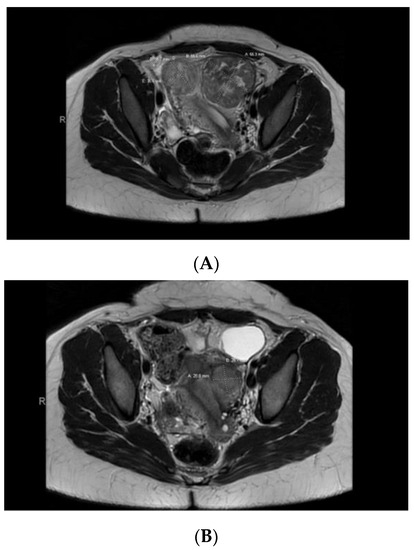

Case 5: A 32-year-old Black patient presented with increased pelvic pressure and urinary frequency. A pelvic ultrasound revealed a 7.5 cm UF and a subsequent pelvic MRI showed a dominant, primarily intramural, anteriorly situated UF measuring approximately 5.6 × 5.5 cm with central degeneration (Figure 4A). AdditionalUFs, including subserosal ones, were noted. The patient underwent a myomectomy with exploratory laparotomy, confirming a leiomyoma with FH deficiency features. Germline genetic testing was positive for a pathogenic mutation in the FH gene, c.239dupA (p.Ile81Aspfs*14). This mutation results in a premature stop codon in exon 2, causing disruption of protein production. A year later, the patient returned with pelvic pain, and a pelvic MRI showed her uterus contained at least 4 fibroids (with a dominant submucosal one), 2 in the right/fundus and 2 on the left (Figure 4B). She chose to undergo a robotic hysterectomy and bilateral salpingectomy, revealing additional FH-d leiomyomas.

Figure 4. (A) Pelvic MRI pre-myomectomy. (B) Pelvic MRI post-myomectomy.